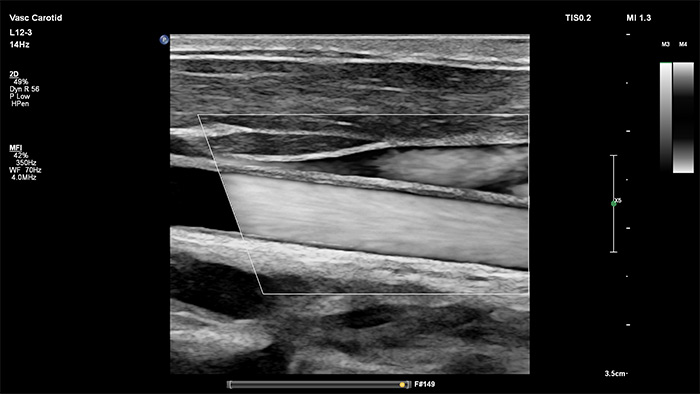

XL14-3 xMATRIXは、xPlaneドプラ機能も備えています。xPlaneパルスドプラは縦断面および横断面の参照画像を使用して、ドプラサンプルボリュームの位置決めを正確に行います。xPlaneドプラの主なメリットには、有意狭窄のサンプリング時に、サンプルボリュームの位置決めエラーを減少させ、高い再現性と一貫性を実現する点が挙げられます。